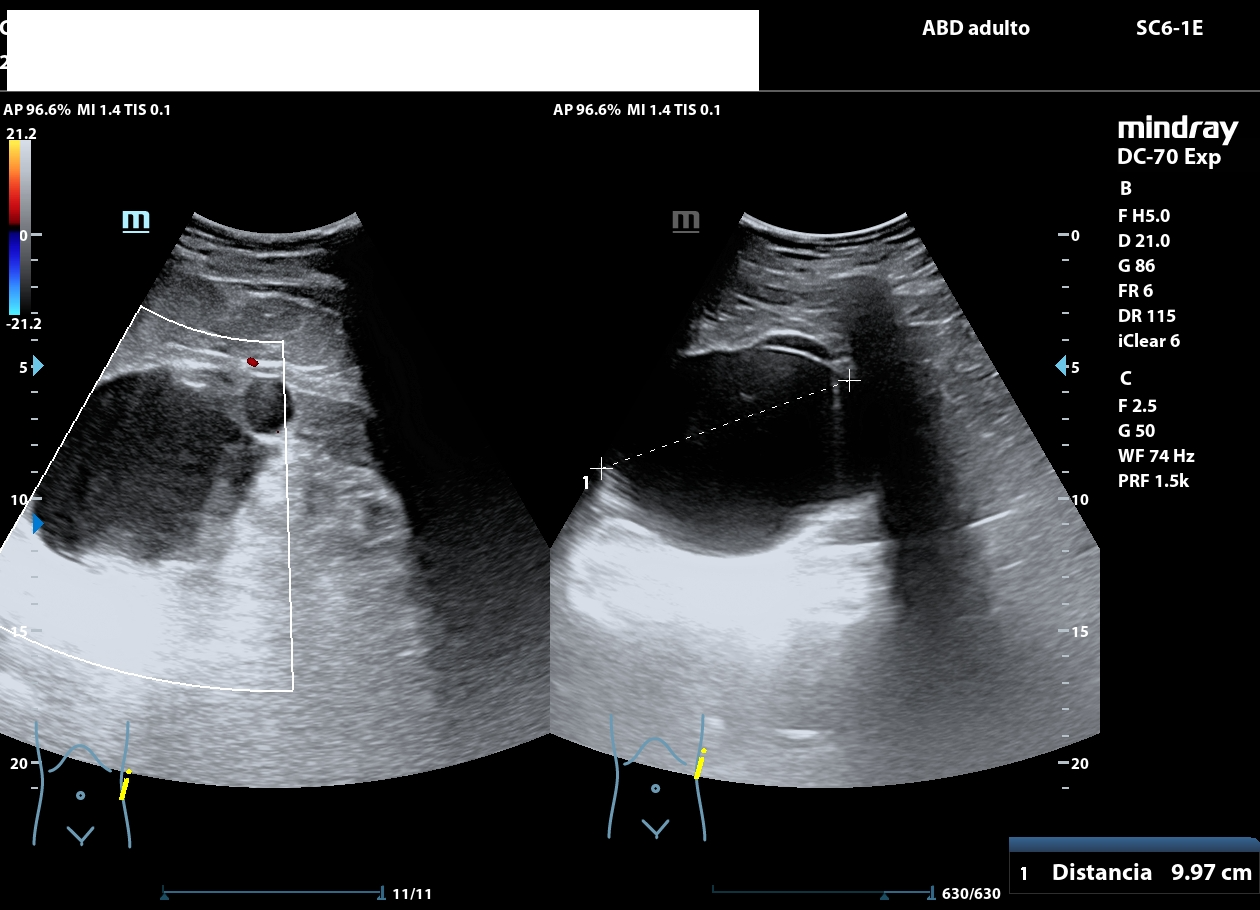

La ecografía abdominal muestra ambos riñones con múltiples quistes corticales y medulares, de diferentes diámetros, distribuidos de forma difusa.

El parénquima presenta un aspecto multiquístico que confiere una morfología global cribo forme, semejante visualmente a un «queso gruyere». No se observan litiasis, ni signos de obstrucción de la vía urinaria.

El quiste de mayor tamaño (aprox. 9 cm) se observa en riñón izquierdo; sin ecos internos, calcificaciones o sextos (categ BosniaK 2). En riñón derecho se aprecian múltiples quistes alguno de ellos con esto grueso en su interior, sin calcificaciones ni componentes sólidos en su interior (categ. BosniaK 2-3).